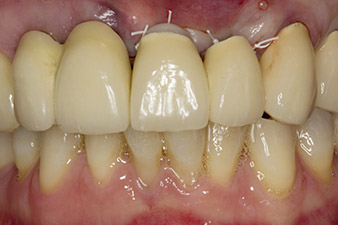

When the patient first presented, teeth 21, 22 and 23 had been restored with splinted crowns, now 19 years old, which were bonded to the implants at positions 12/11 by an attachment (cf. Fig. 2).

Following primary healing, the soft tissues were shaped using the basally lined bridge. Two months later the site was exposed by a slightly palatal alveolar ridge incision (Fig 2). The dimensions of the alveolar bone proved to be sufficient at position 22. Figures 2 and 4 show the preparation of the implant bed, the tapping and the implantation using Implantmed.

In this case study, the situation was resolved with an implant at position 22 in the first procedure and an additional one at the position of the extracted tooth 23 later in the course of the treatment. The second implant was inserted following successful osseointegration of implant 22. The revised bridge was reinserted until implant 23 healed in place and the shaping for the permanent restoration was complete. The advantages of this gradual approach include the implants’ being able to accept loads more resiliently and mature hard and soft tissues (5).